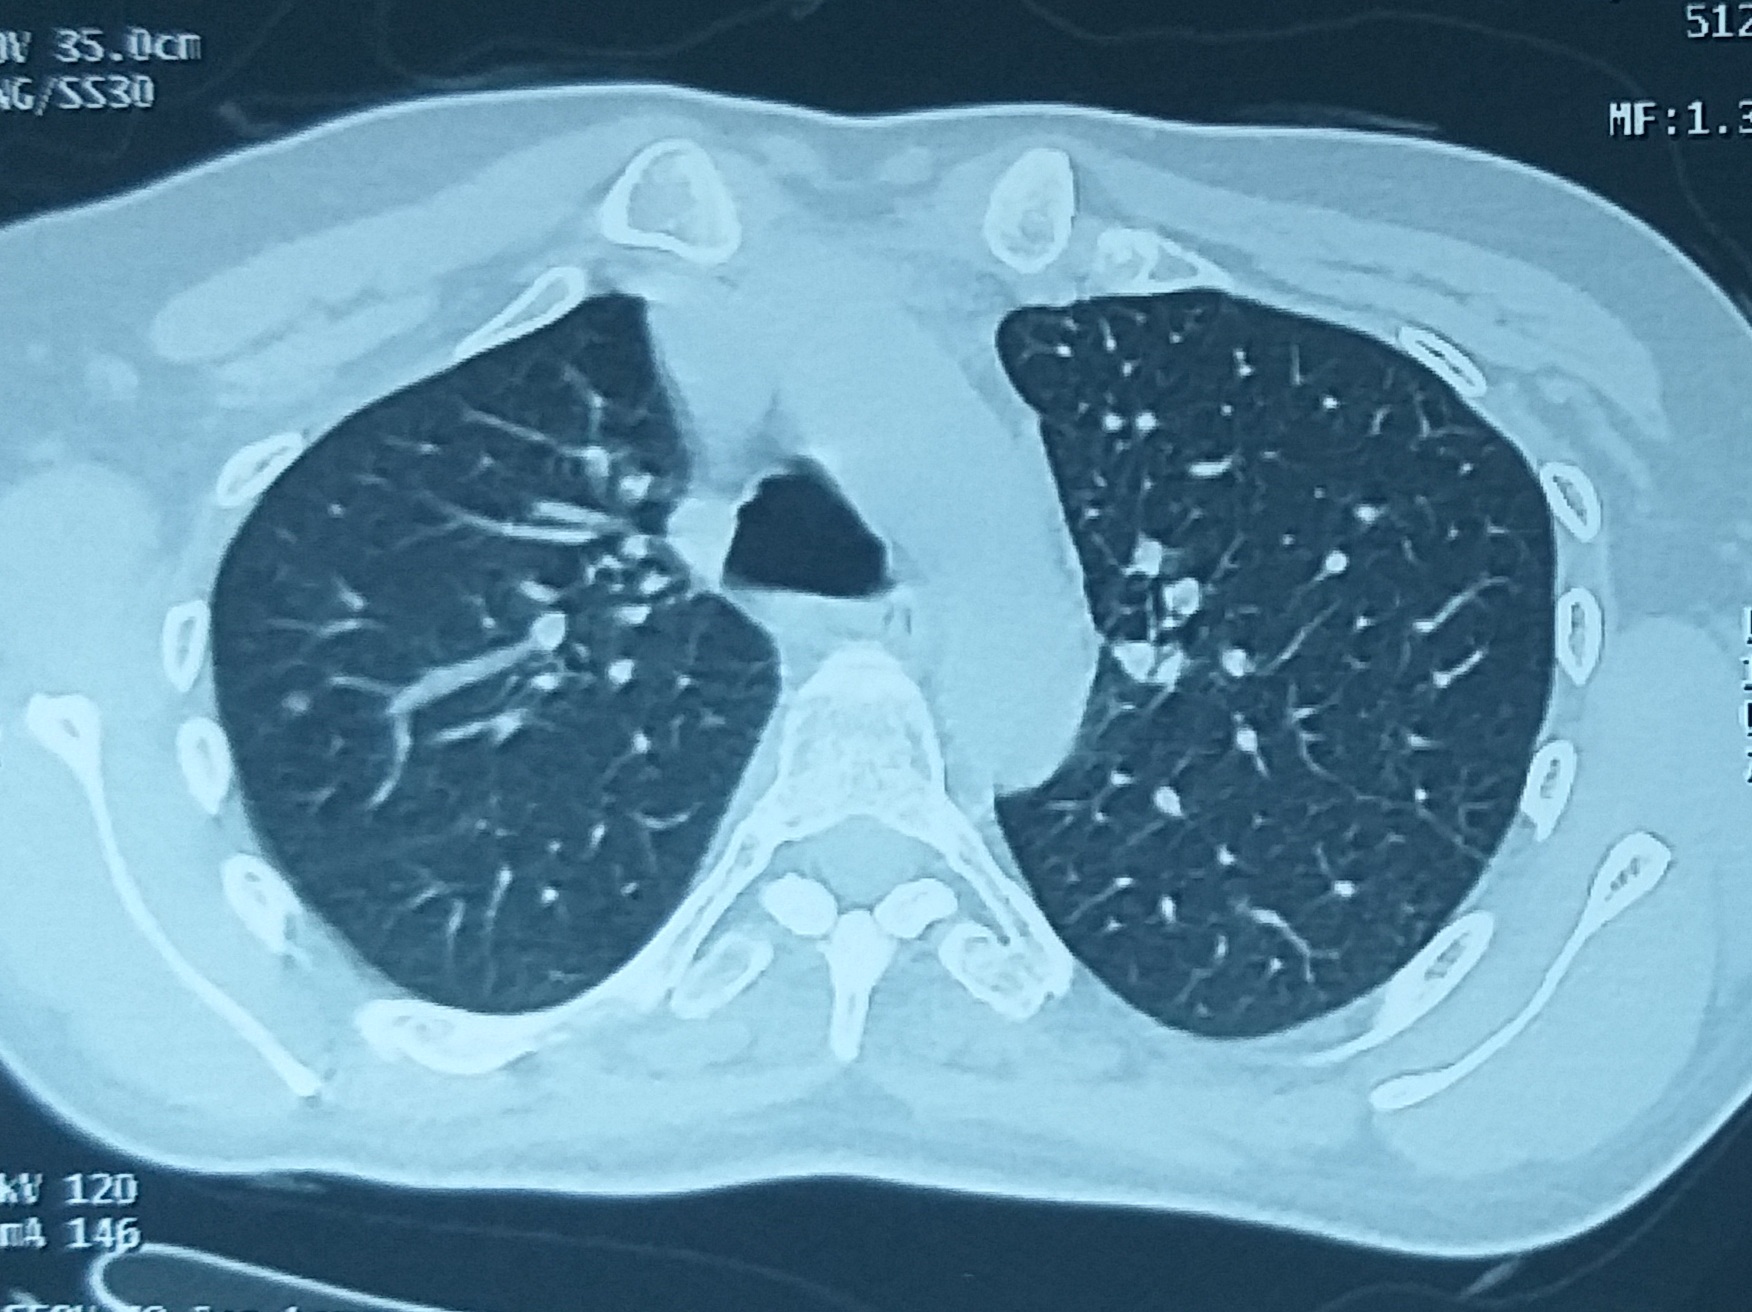

Ankylosing spondylitis is a chronic inflammatory disease affecting the young men and less commonly women with a spectrum of manifestations including uveitis, arthritis, sacroiliitis, colitis and psoriasis (spondyloarthropathy). Mixed connective tissue disorder (MCTD) is a complex and heterogenous autoimmune disease that affects women in their childbearing age. It is characterized by circulating autoimmune antibodies that deposit in tissues, resulting in inflammatory response, causing irreparable tissue damage. Overlap and co-existence of these diseases are uncommon, as per literature evidence. The present study has reported the case of a 35-year-old female, who had HLA B27-positive spondyloarthropathy for 10 years and had been receiving sulfasalazine, and had neck swelling for 4 months. Screening conducted for TB in view of fever, weight loss and neck nodes, had reported negative results. She was found to have Reynaud’s disease, arthritis, bilateral cervical lymphadenopathy and elevated autoantibody titers including ANA, U1SM/RNP and Coombs-positive hemolysis. The diagnosis was concluded as MCTD and she had responded well to the treatment. As per the available literature, this could be touted as the first case study of a female patient with ankylosing spondylitis and MCTD.